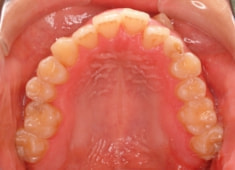

治療後(2年1ヶ月後)

下顎の右側への偏位は解消されました。

大臼歯は整直されております。

歯根のパラレリングは良好です。

左上2番の歯根も問題なさそうです。

下顎8番は保定期間に入り、しばらくして咬合が安定してから抜歯する予定です。